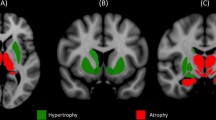

T1-weighted image preprocessing

Voxel-based morphometry (VBM) analysis was used to assess the volume difference between the ET and HC groups. We used the CAT12 Toolbox (Computational Anatomy Toolbox; http://dbm.neuro.uni-jena.de/cat12/) running in SPM12 (Statistical Parametric Mapping) software (www.fil.ion.ucl. ac.uk/spm) to conduct VBM. The preprocessing steps were [15] (a) All images were corrected for noise, inhomogeneities, and intensity, and then divided into WM, GM, and CSF components; (b) The divided images were normalized into a standard MNI space with the Diffeomorphic Anatomic Registration Through Exponentiated Lie algebra algorithm; (c) Spatial normalized images were adjusted to ensure the relative GMV; and (d) Weighted overall image quality algorithms, Mahalanobis distance, and mean correlations were used to quantify image quality [subjects who fell below the quality threshold (2 SDs) were removed]; (e) Subsequently, the total intracranial volume (TIV) was estimated before being smoothed; and (f) Finally, images were smoothed using a 6 mm full-width-half-maximum isotropic Gaussian kernel.

GBSS analysis showed that the MK value was significantly lower in the ET than the HC groups in temporal lobe (bilateral Temporal gyrus, bilateral Angular gyrus and bilateral Fusiform gyrus), parietal lobe (right Superior and inferior parietal gyrus, left parietal gyrus, bilateral Supra marginal gyrus, right postcentral gyrus and bilateral Cuneus), occipital lobe(bilateral occipital gyrus and left lingual gyrus) and cerebellum (bilateral Cerebellum 6,7b,8,9, left Cerebellum 4,5, Vermis 6,7, bilateral Cerebellum_Crus 1,2 and left Cerebellum_Crus 4,5,6) (Specific clusters are shown in Fig. 1 and Table 2). No significant differences in AK or RK values were found between the ET and HC groups, and no significant difference in GM volume was found between the two groups.

This study compared the differences in GM structure between the patients with ET and the HCs using the GBSS. We observed lower MK values in the cerebellum, occipital lobe, temporal lobe, and parietal lobe of patients with ET. MK is the most commonly used dispersion kurtosis parameter in clinical research. MK represents the overall microstructure complexity of brain tissue. Disintegration of axons and loss of cell bodies lead to a loss of microstructural complexity and an increase in extracellular free diffusion space, which are eventually manifested as a decrease in MK [10, 16]. Therefore, the decrease in MK values represents changes in GM microstructure, which may be due to neurodegeneration, including changes in the structure of the axons of Purkinje cells, and decreased dendrite spines and cell densities [17]. However, these changes do not necessarily cause observable volumetric differences on structural imaging. No significant structural changes were observed in the T1 phase of this study. Although previous studies have found that patients with ET have volume loss and cortical thickness changes of cerebrum and cerebral cortex, the samples of these studies are relatively small and the results are not consistent. Therefore, we believe that volumetric changes may not be sensitive enough compared to microstructural changes based on diffusion imaging, or that microstructural changes occur earlier than gray matter atrophy. These results also suggest that DKI is a sensitive means to detect ET damage and a potential imaging marker to identify ET.